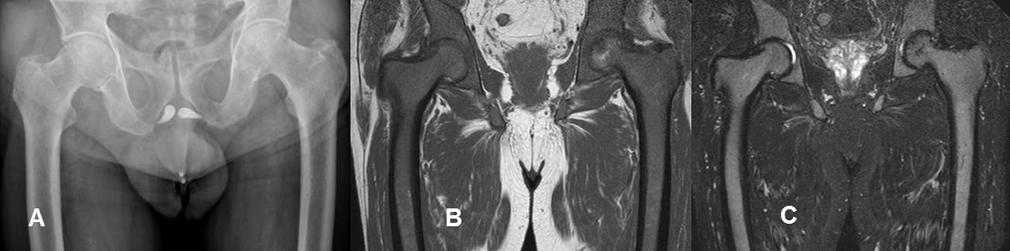

Fig 12 C. Mielodisplasia.

A: Rx AP. No se identifican lesiones focales, ni alteración en la densidad ósea.

B: RM coronal en T1 y C: RM coronal en STIR. Alteración en la señal, con predominio de medula ósea roja hipointensa en T1, en un paciente afectado por mielodisplasia.